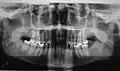

Su nombre, radiografía intrabucal, se debe, naturalmente, a que las películas se colocan dentro de la cavidad bucal. Según el tamaño y la colocación de las películas, se pueden clasificar en procedimientos periapicales o retroalveolares, interproximales o de aleta mordida y oclusales. Un requisito imprescindible previo para la realización de la radiografía intrabucal es retirar prótesis metálicas removibles, dispositivos ortodóncicos o cualquier objeto metálico que se encuentre en el área a estudiar. Además, es necesaria la inmovilización perfecta de la cabeza del paciente en la posición idónea.

- Las técnicas periapicales o dentoalveolares, sirven para explorar el diente en su totalidad, desde la corona hasta el ápice, el espacio periodontal y el tejido óseo que lo rodea. Se puede realizar mediante dos procedimientos: la técnica de bisectriz y la de planos paralelos.

Radiografía intrabucal: técnicas interproximales o de aleta mordida

- Las técnicas interproximales o de aleta mordida son muy útiles para el estudio sistemático y la exploración de la caries dental. Se aprecian caries interproximales y oclusales, pero también alteraciones pulpares, restauraciones desbordantes, recidivas de caries bajo éstas, ajustes de prótesis fijas, cresta alveolar, límite amelocementario…en una misma película se observan las regiones coronal y cervical de los dientes superiores e inferiores a la vez. El examen es cómodo y rápido, ya que las películas no se clavan en el suelo bucal; por este motivo es una exploración habitual para la detección de caries interproximales en niños.

- Las técnicas oclusales se denominan así porque la colocación y sujeción de la película se realizan en el plano oclusal, entre el maxilar y la mandíbula, dirigiéndose el haz de rayos desde arriba o desde abajo, perpendicular u oblicuamente. Se utilizan como complemento de los procedimientos periapicales, para estudios más amplios de áreas óseas, fracturas alveolares, palatinas o del cuerpo mandibular, límites de lesiones quísticas o tumorales, dientes incluidos y cuerpos extraños.